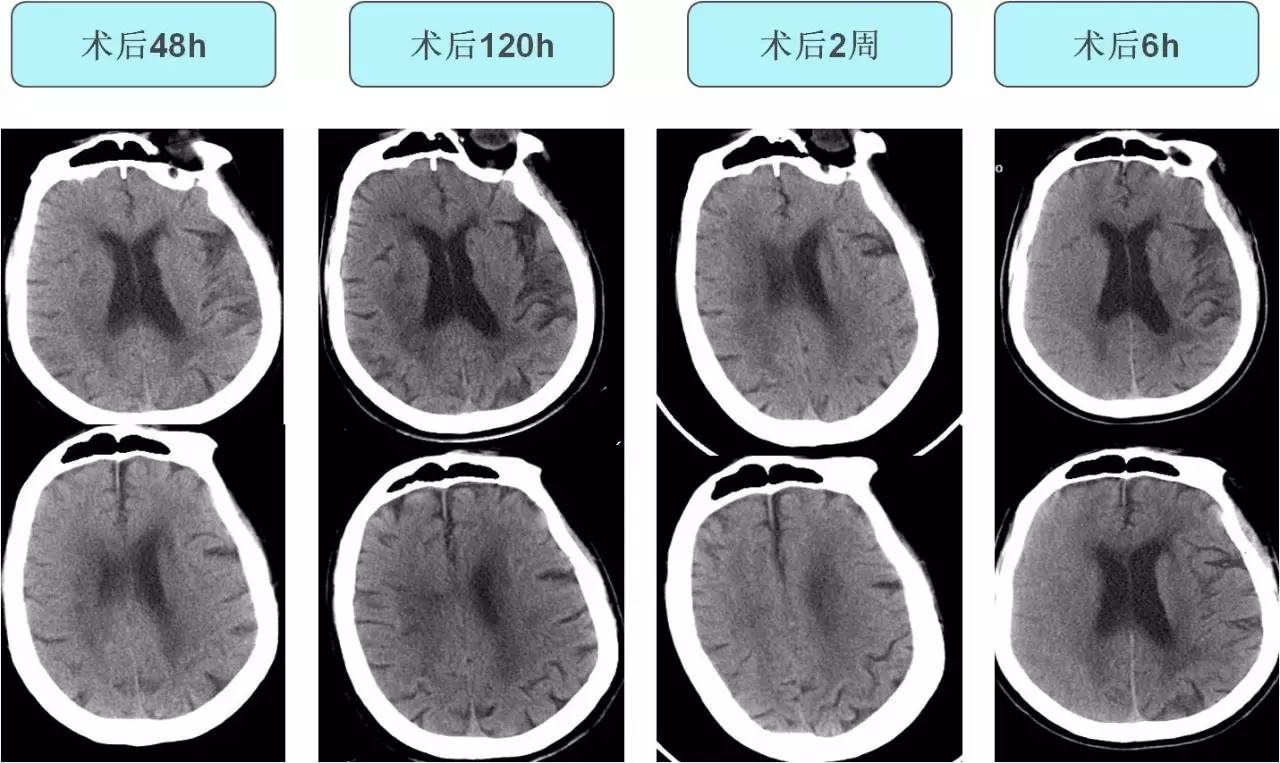

不同时间CT表现

》术后10h出现发热,体温最高达38.8℃,无头痛,无恶心、呕吐,无肢体抽搐。查体:浅昏迷,双眼左侧凝视,右侧肢体肌张力低,疼痛刺激无反应,右侧巴氏征阳性。

诊断及治疗